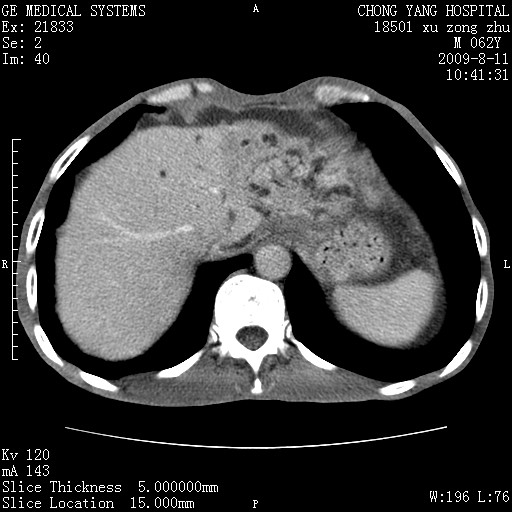

以下是引用杀毒软件在2009-8-11 16:35:00的发言:[br]肝内胆管扩张局限于左叶,胆管内有结石伴肝外胆管结石,胆管壁增厚呈弥漫性并发腹腔积液,胰腺边界模糊。[br][br]考虑---胆总管及肝内胆管结石继发胆管炎及胰腺炎,左肾下极囊肿,腹水。

以下是引用zjzjr在2009-8-11 17:35:00的发言:[br]肝内胆管扩张局限于左叶,胆管内有结石伴肝外胆管结石,胆管壁增厚呈弥漫性并发腹腔积液。[br][br]考虑---胆总管及肝内胆管结石继发胆管炎,左肾下极囊肿,腹水。